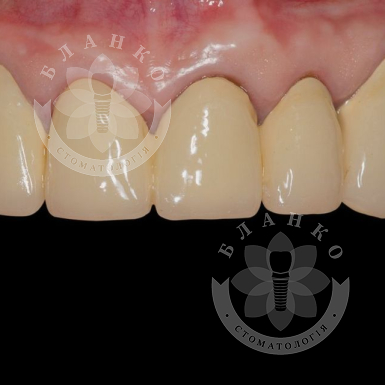

植牙 —這是修復缺牙的現代且可靠的解決方案。在Blanco牙科診所,我們提供交鑰匙牙種植,這意味著全方位的服務 —從診斷到安裝牙冠,沒有隱藏費用或意外開支。